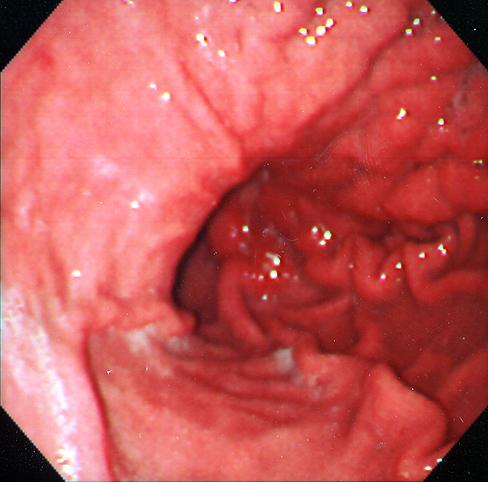

疾患(病理主体)の分類悪性上皮性腫瘍/腺癌

部位(臓器別)胃(部位)/2つ以上

検査方法内視鏡

腫瘍の肉眼分類4型(びまん浸潤型)/

病変の最大径(ミリ)40以上

腫瘍の深達度s(a)